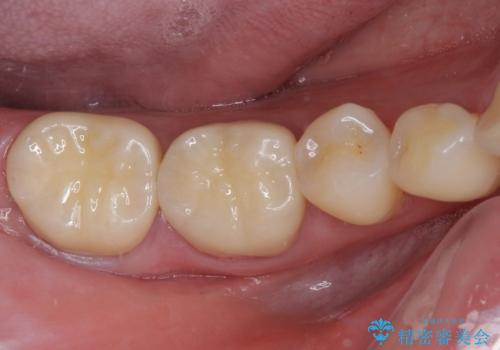

歯肉が退縮したことで見えていた歯根もセラミッククラウンで覆うことができ、清掃性も改善されました。